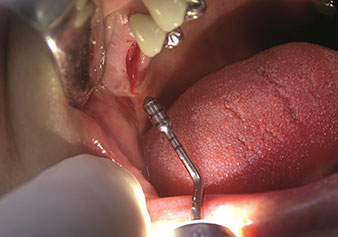

Internal sinus lift

W&H also offers the perfect solution for the internal sinus lift.

Following preparation of the maxillary sinuses with the corresponding instrument set (Fig. 3), the new Z35P instrument (Fig. 4) is used to lift the membrane hydrodynamically. The same instrument set can also be used for piezosurgical preparation of the implant bed in increasing diameters (Figures 3 and 4 included with the kind permission of Dr Mario Kirste, Frankfurt/Oder).

Preparation of implant bed with I4P instrument

Fig. 3: Preparation of implant bed with I4P instrument. Photo: © Dr Mario Kirste (Frankfurt / Oder)